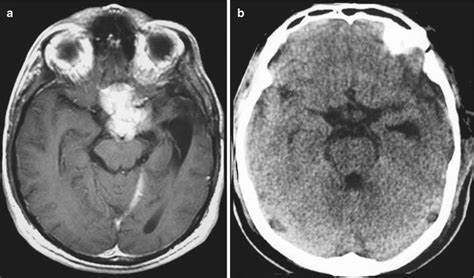

计算机断层扫描是一种明确的诊断方法,它显示肿瘤是一种均匀增强的肿块,边界清晰。

核磁共振成像,是对比,可以较好地显示脑膜瘤及其与神经和血管结构的关系。